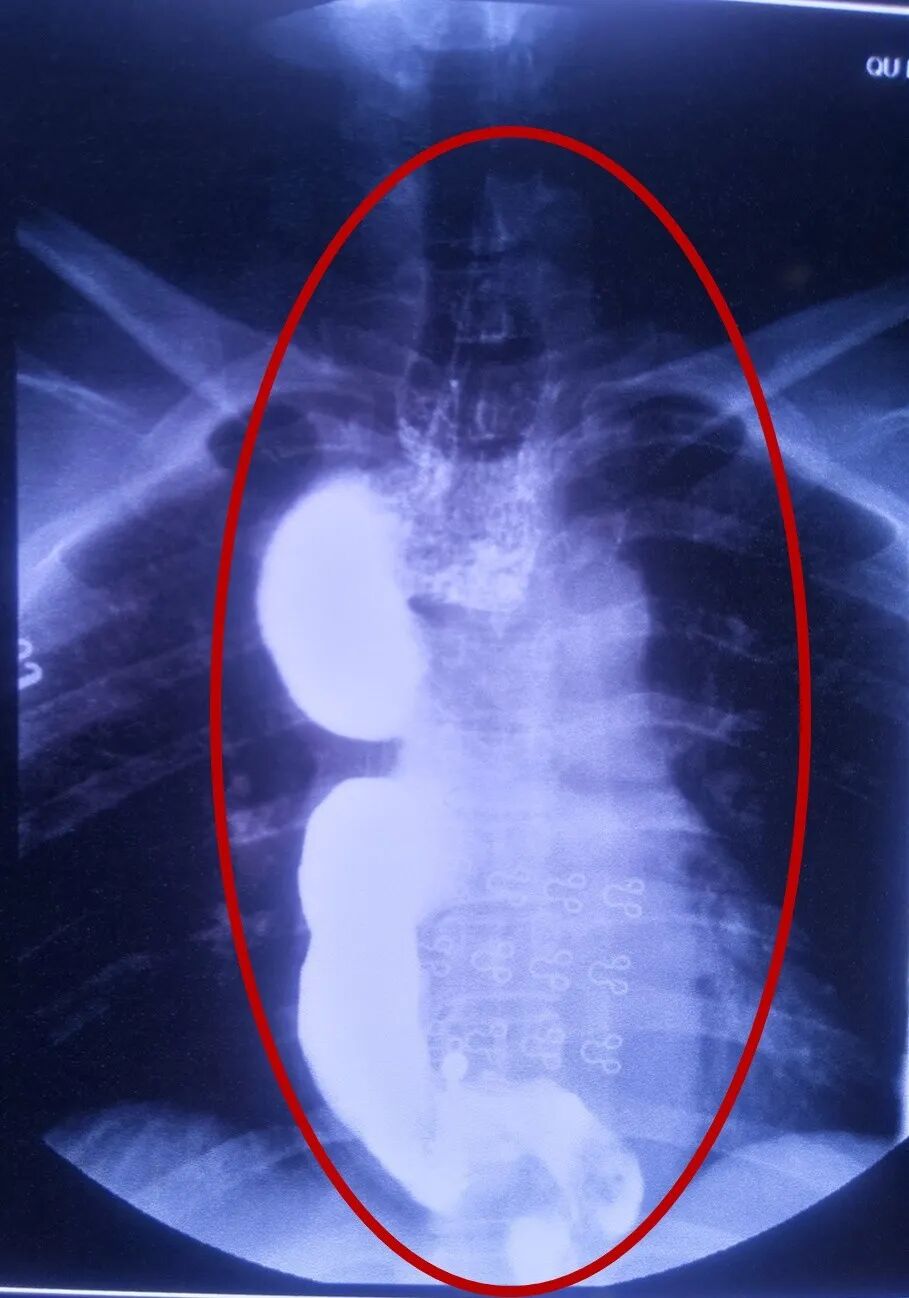

术前全段食管水肿变宽肥厚

结合患者诉求,经科室医师集体讨论,并请山东省立医院胸外科李军教授会诊后,科室精心制定了治疗方案。3月22日,在介入下行十二指肠营养管置入术,改鼻饲流食,使扩张食管得以修复回缩。5月23日,全麻下给予改良食管肌层切开术[改良Heller手术],术后在胸外科全体医护人员的精心治疗护理下,术后恢复良好。